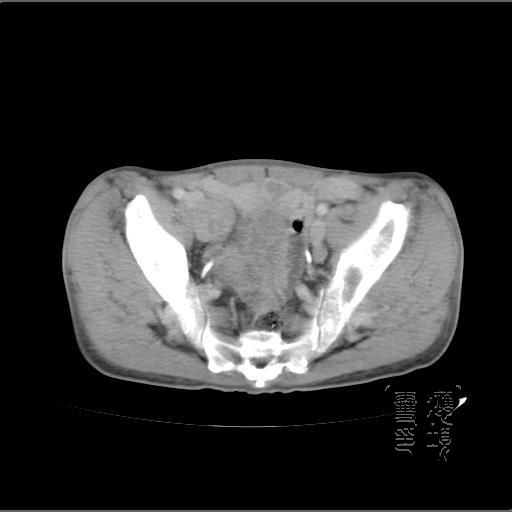

以下是引用dyqct在2007-4-20 20:51:00的发言:[br]考虑:1、右侧膀胱外上方实性富血管性肿瘤(神经鞘膜瘤?纤维瘤?巨淋巴结增生症?)[br] 2、请标识需要解释的地方。

以下是引用aa13877358820在2007-4-21 7:01:00的发言:[br]隐睾?